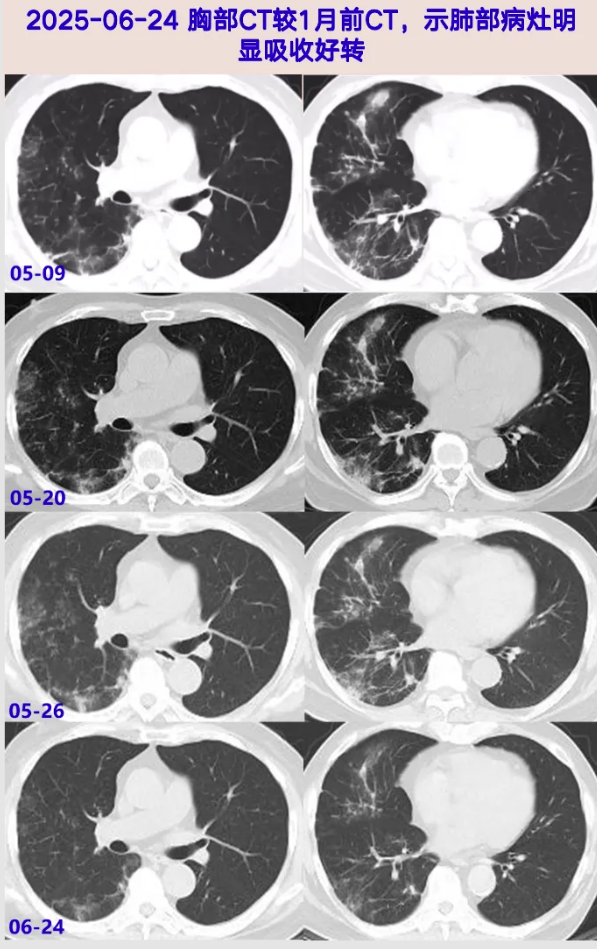

2025-05-26 肺组织病理免疫组化及特殊染色:考虑真菌感染,隐球菌可能;随访血常规:WBC 9.68×10^9/L,N 80.5%,L 1.2×10^9/L,Hb 80g/L;炎症标志物: ESR 28mm/h,hsCRP 19.6mg/L,PCT 0.09ng/mL;Cr 206μmol/L ;胸部CT:右肺为著多发炎性病变,较05-20大致相仿。

2025-06-24 随访血常规:WBC 13.53×10^9/L,N 77.3%,L 1.9×10^9/L,Hb 108g/L,PLT 171×10^9/L;炎症标志物: ESR 28mm/h,hsCRP 1.2mg/L,PCT 0.1ng/mL ;Cr 242μmol/L;胸部 CT:右肺为著多发炎性病变,较05-26局部吸收,嘱患者随访血隐球菌荚膜抗原,继续随访中……

中老年男性,慢性病程,胸闷起病,无明显其余伴随症状,因肾病长期口服激素治疗,炎症指标无明显升高,胸部CT见右肺为主多发斑片影,血及BALF隐球菌荚膜抗原滴度显著升高,BALF mNGS检出新生隐球菌、耶氏肺孢子菌(序列数少,且与患者症状及后续治疗结果不符)、CMV-DNA及EBV-DNA,肺组织病理特殊染色见PAS及六胺银(+),肺组织培养新生隐球菌(+),完善腰穿颅内压正常,脑脊液常规、生化、病原学及细胞学检查均阴性,氟康唑治疗1月后肺内病灶较前吸收好转,综上新型隐球菌肺炎诊断明确。